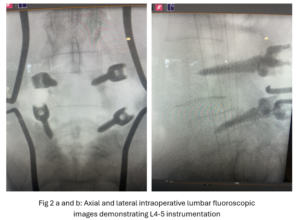

This 54-year-old female with a long history of low back pain presents with three weeks of a progressive right footdrop with associated numbness and tingling of the right leg. In addition, she had right lateral hip pain down to the dorsum of her foot. She first noticed her right foot slapping the floor when she walked. She had no prior trauma or unusual activity before this began. Her chiropractor, who had treated her back pain for a long time, first noticed the foot drop and referred her for further evaluation. She presented with ⅖ strength in her right dorsiflexor. MRI revealed a large right L4-5 foraminal synovial cyst with some mass-effect on the thecal sac. (Fig. 1) She also had an associated grade 1 spondylolisthesis. Because the cyst was more foraminally-oriented, it had the majority of its effect on the right L4 nerve root. It was felt the patient required surgery to attempt to reverse her weakness. We performed a decompressive laminectomy at L4, removing the inferior facet process on the right in order to gain lateral and foraminal access to the right L4 nerve root. In the lateral recess there was a heap of inflammatory tissue which we entered, revealing the cyst. The medial wall was stuck to the dura. We internally decompressed the cyst which was mainly gelatinous material with some fluid. We dissected and removed as much of the cyst we could safely remove but left the medial wall for fear of removing it would cause a CSF leak, upon removing the bulk of the cyst we encountered anteriorly the descending and exiting right L4 nerve root which was purplish in color and clearly inflamed. We performed a generous foraminotomy of the right L4 as well as the right L5 nerve root. We also performed an instrumented fusion at L4-5 (Fig. 2).

This 50-year-old female with a long history of low back pain and a prior history of multiple lumbar surgeries with instrumentation. She had a L3-5 laminectomy with instrumentation about 7 years prior and now presents with progressive worsening of low back pain. The pain was worse with activity, standing, walking, and prolonged sitting. She had an MRI which showed next segment degeneration at L2-3 with stenosis and the development of a large posteriorly-oriented synovial cyst with thecal sac compression (Fig. 3). The patient failed all means of conservative management including physical therapy and epidurals. We decided to perform an L revision laminectomy to decompress and remove the cyst as well as explore her prior fusion. In this case, again the anterior wall of the sac was completely stuck to the dural membrane. Therefore, we internally decompressed the cyst which was mainly degenerated, necrotic material and removed as much wall of the cyst that could be safely removed. There was some fluid within the cyst. Of note during the dissection of these cysts there is often a release of cyst fluid the patient was well-decompressed. We removed the prior instrumentation and added a new L2-3 construct (Fig. 4). The patient had an uneventful hospital course and was discharged on post op day 2.